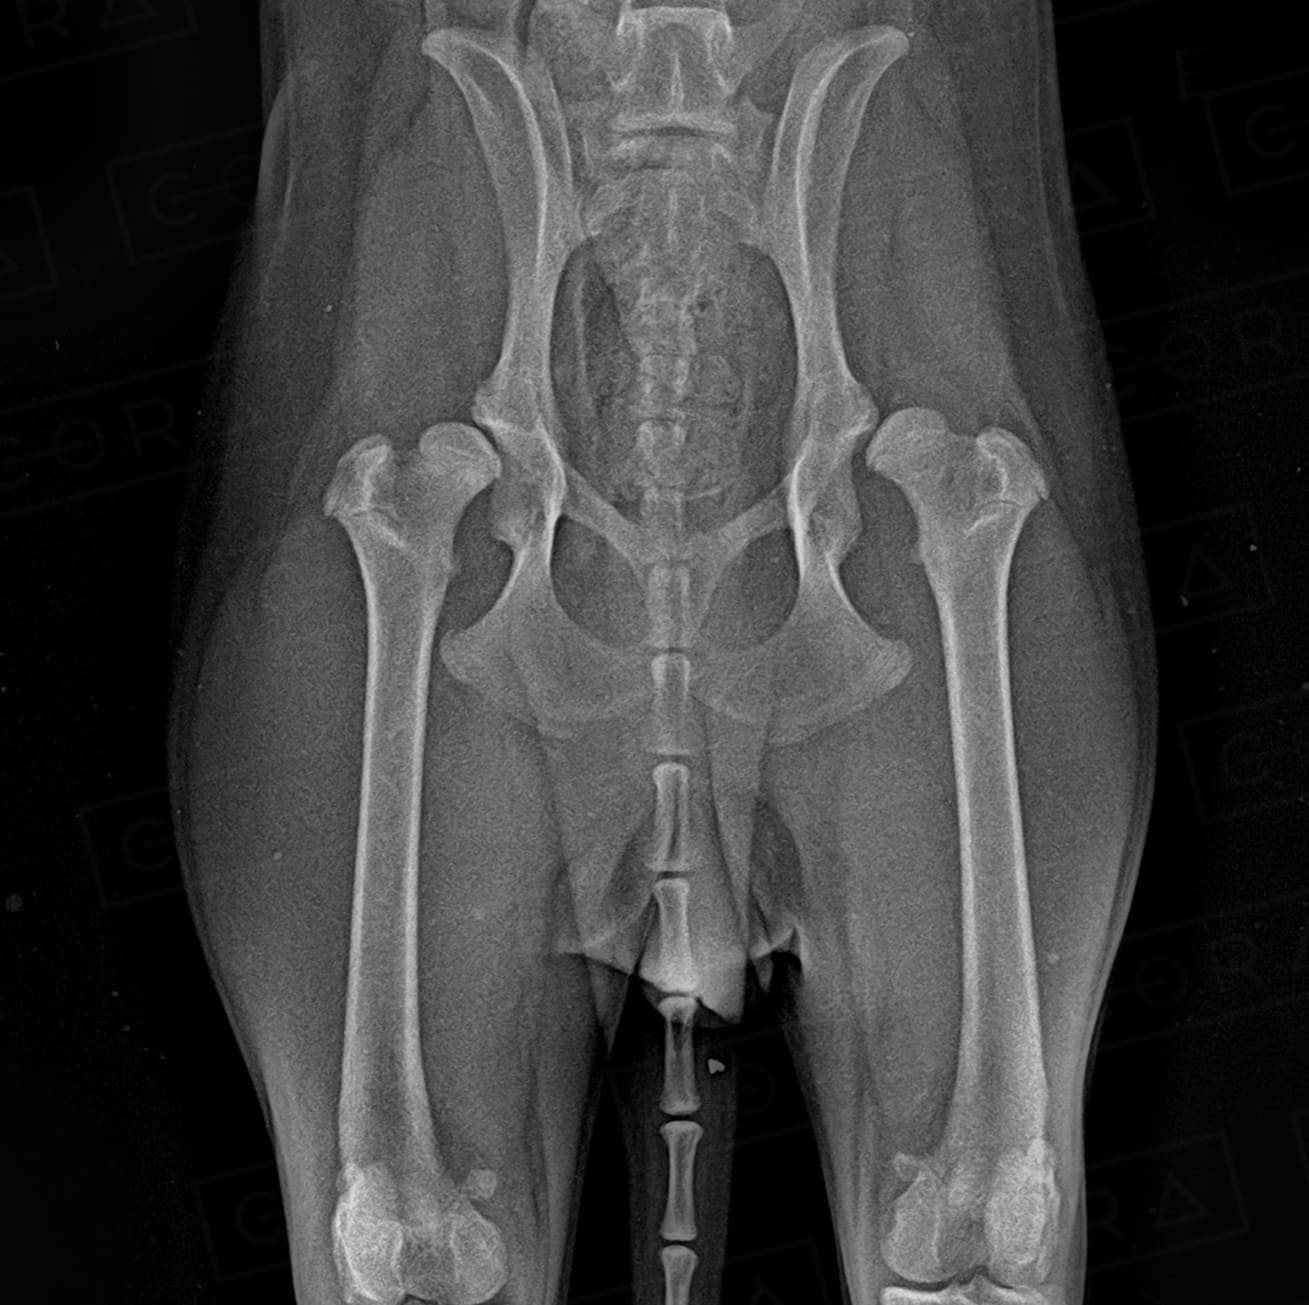

DISPLASIA COXOFEMORAL

A sinais clínicos (DCF) é uma doença de característica genética e poligênica envolvendo uma ou ambas as articulações do quadril, causada pela instabilidade do quadril, levando a incongruência articular e desenvolvimento de osteoartose.

O diagnóstico é baseado na anamnese, exame físico e radiográfico simples. O diagnóstico precoce, em filhotes ainda assintomáticos, pode ser feito por meio do PennHIP, técnica de raio-x por distração articular, que estima o grau de instabilidade do quadril e risco de desenvolvimento de osteoartrose. O diagnóstico precoce possibilita um melhor prognóstico e mais qualidade de vida ao animal.

4. Osteotomia Dupla ou Tripla de Pelve (ODP ou OTP)

Técnica preventiva para cães até 8 meses de idade, usada para aumentar a cobertura acetabular sobre a cabeça do fêmur para impedir ou minimizar a subluxação do quadril e subsequente desenvolvimento da osteoartrose. Vários pré-requisitos são necessários para a escolha dessas técnicas.